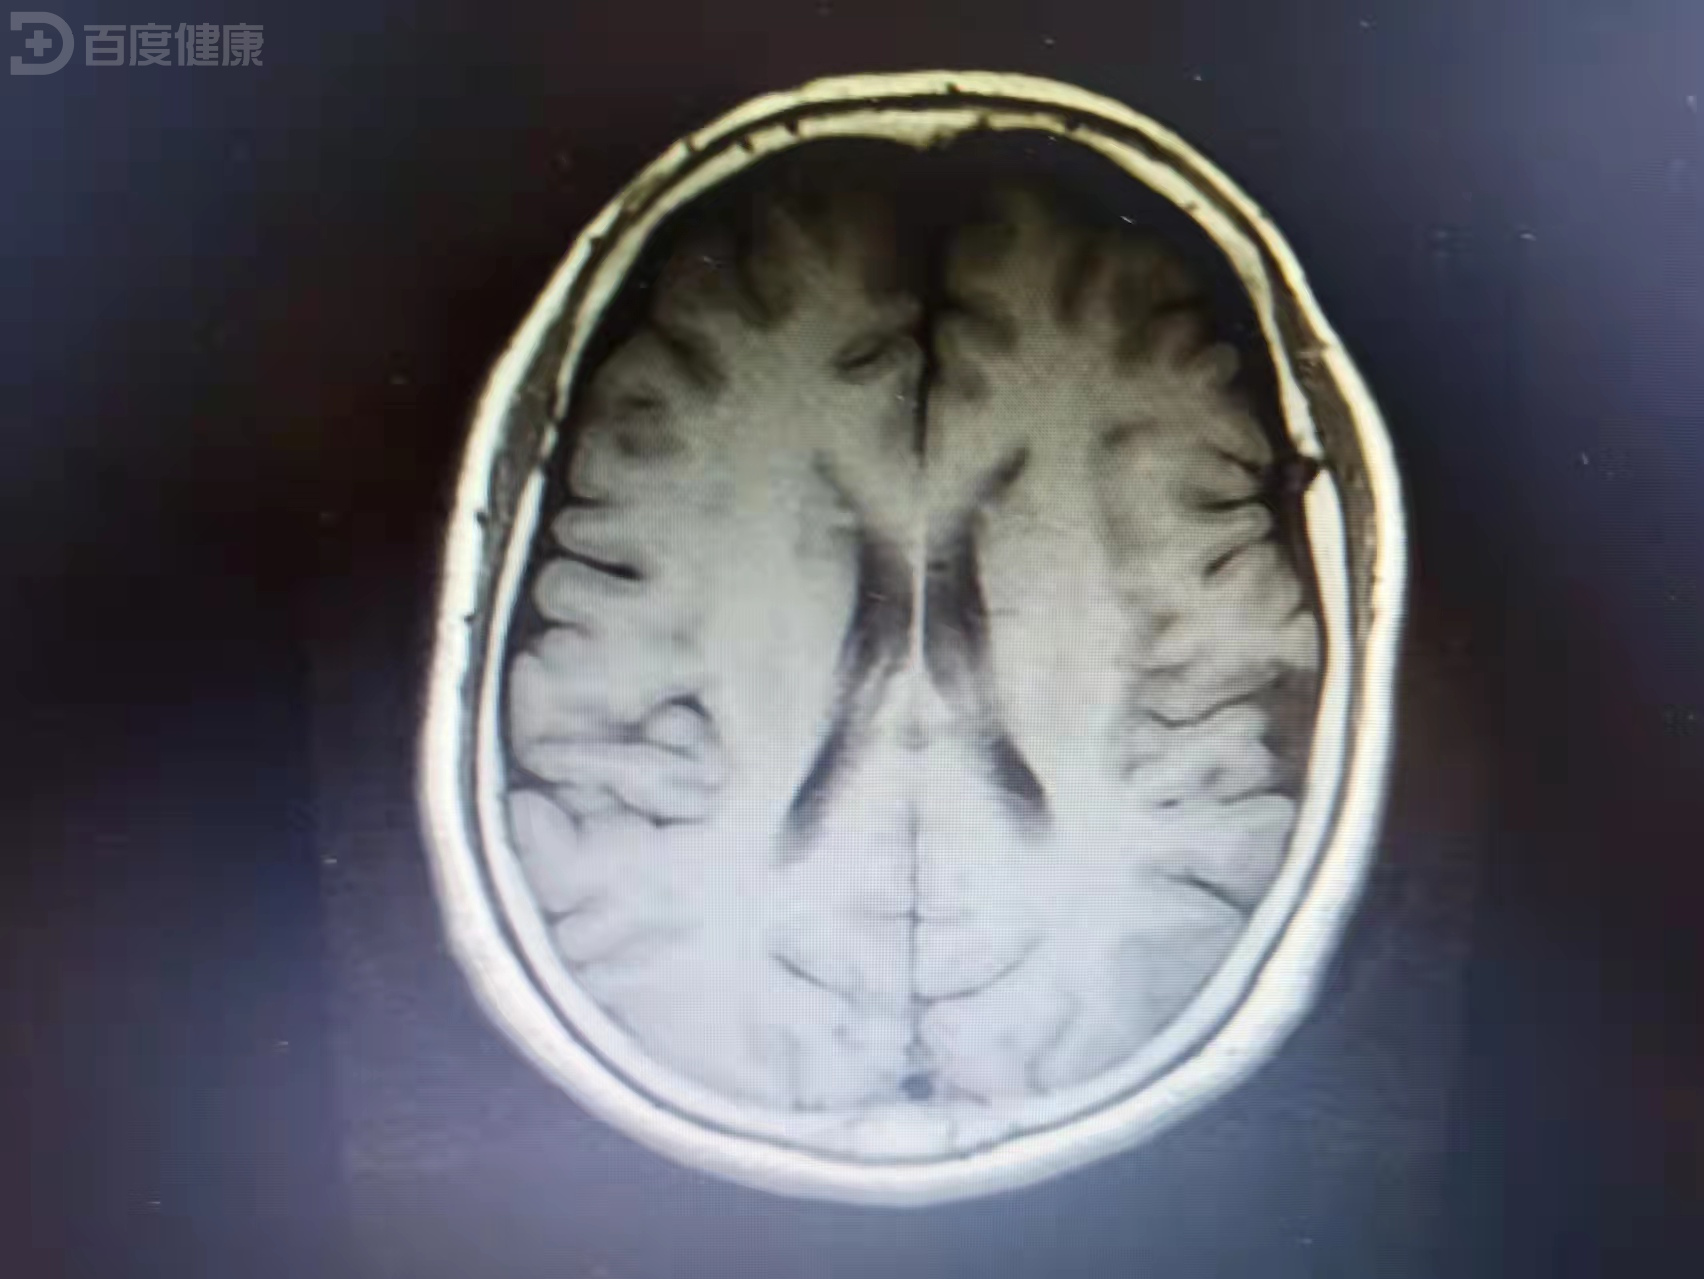

他临时抽调两名经理进修学习,自己则代为效劳。距上次那通电话已过去三月有余,在此期间,迟烨再没有联络过周御璋,周御璋也不愿无故打搅迟烨生活,因而只要求助理密切关注医院方面动向。老话讲,由奢入俭难,更何况是天翻地覆的巨变,/视/察/前,周御璋设想过迟烨的状态难免消沉。集团总裁亲自视察,领导召集全体员工等候讲话,周御璋有心留意,一眼就发现站在人群中的迟烨。 迟烨身穿工作服,头戴安全帽,出乎意料,他的脸色和精神都恢复得不错。午休,周御璋到工厂食堂用餐,他远远望见迟烨与同事边打饭边聊天,用完午饭,周御璋/视/察/各部门,他走至库房区域看见迟烨站在厢式货车内拆卸集装箱。迟烨的袖管挽到肘部,他明显黑了瘦了,但脸上始终带着明媚的笑。下午,周御璋还另有行程,分工厂领导去为他叫司机,周御璋低头处理工作信息,他听到脚步声,迟烨急匆匆朝他跑过来。迟烨从工作服口袋里掏出盒热牛奶,周御璋勾唇笑了笑,迟烨怯怯地把热牛奶递向他。周御璋推了下鼻梁上的镜架,问迟烨工作累不累,迟烨涨红脸答,不累不累,谢谢您。这天过去,周御璋再见迟烨已是半月后,地点还是医院。事情的原委很简单,分工厂库房屡屡失窃,造成/经/济/损/失/,迟烨为捉到内贼将排班调到傍晚,内贼果真故技重施,迟烨决定抓现行,可谁知内贼随身携带木质棒球棍。迟烨头部受伤,中度脑震荡,周御璋守在病房外,他派助理负责照料。病房饮水机里是开水,迟烨脚步虚浮,动作迟缓,双手端不稳瓷杯,病房门嵌块窄玻璃,助理尚未作出反应,周御璋寒着脸破门而入。迟烨彻底愣住,周御璋将瓷杯放去旁边,不由分说,拦腰把迟烨横抱回病床。